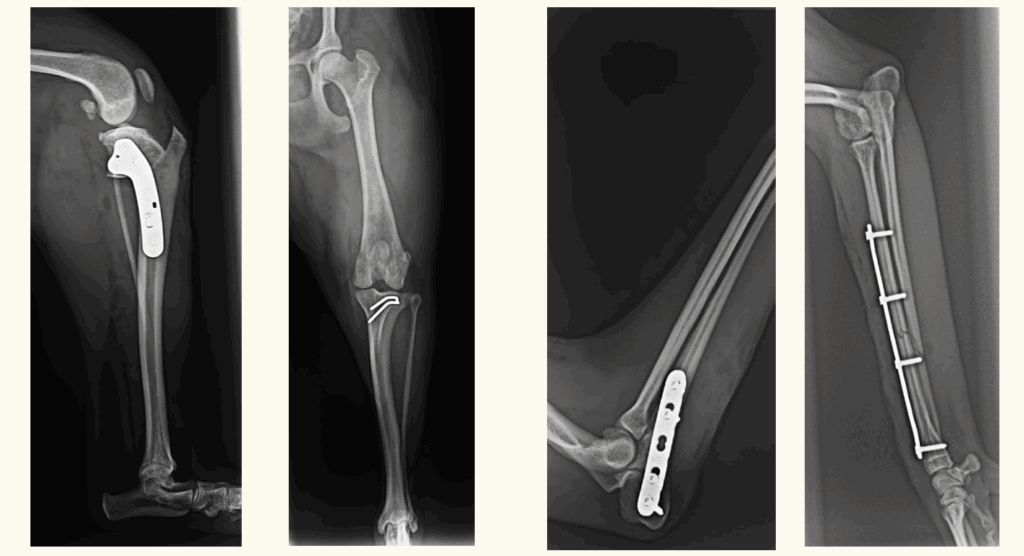

専門性の高い獣医師を招聘しての整形外科手術

当院では、外部の提携獣医師を招聘して整形外科手術を実施しています。

提携獣医師により、当院で質の高い整形外科手術が可能です。

骨折・脱臼など、手術が必要な状態だが、かかりつけの動物病院では整形外科手術を行っておらず、紹介先も遠方で困っているという飼い主様や、整形外科は専門外だが紹介できる二次診療が遠方で困っているという近隣の動物病院の先生方は、当院での手術をご検討ください。